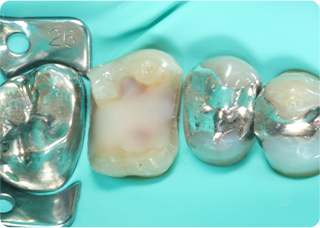

セラミックアンレー症例②

術前

むし歯除去&IDS

ラバーダム防湿

術後

| 主訴 | 右下奥歯の銀歯を白くしたい |

| 治療期間/回数 | 2週間、2回 |

| 価格(税込) | 143,000円(税込) |

| リスク・副作用 | セラミックの破損、一時的な知覚過敏が生じる場合がある |

| ポイント | 銀歯の中はむし歯になっていた。金属イオンにより歯の内部に黒い部分があるが、むし歯を染め出すう蝕検知液を使用し、選択的にむし歯のみを除去。また、セラミック装着時にラバーダム防湿を行うことで、詰め物の接着効果を最大限発揮できるようにした。 |